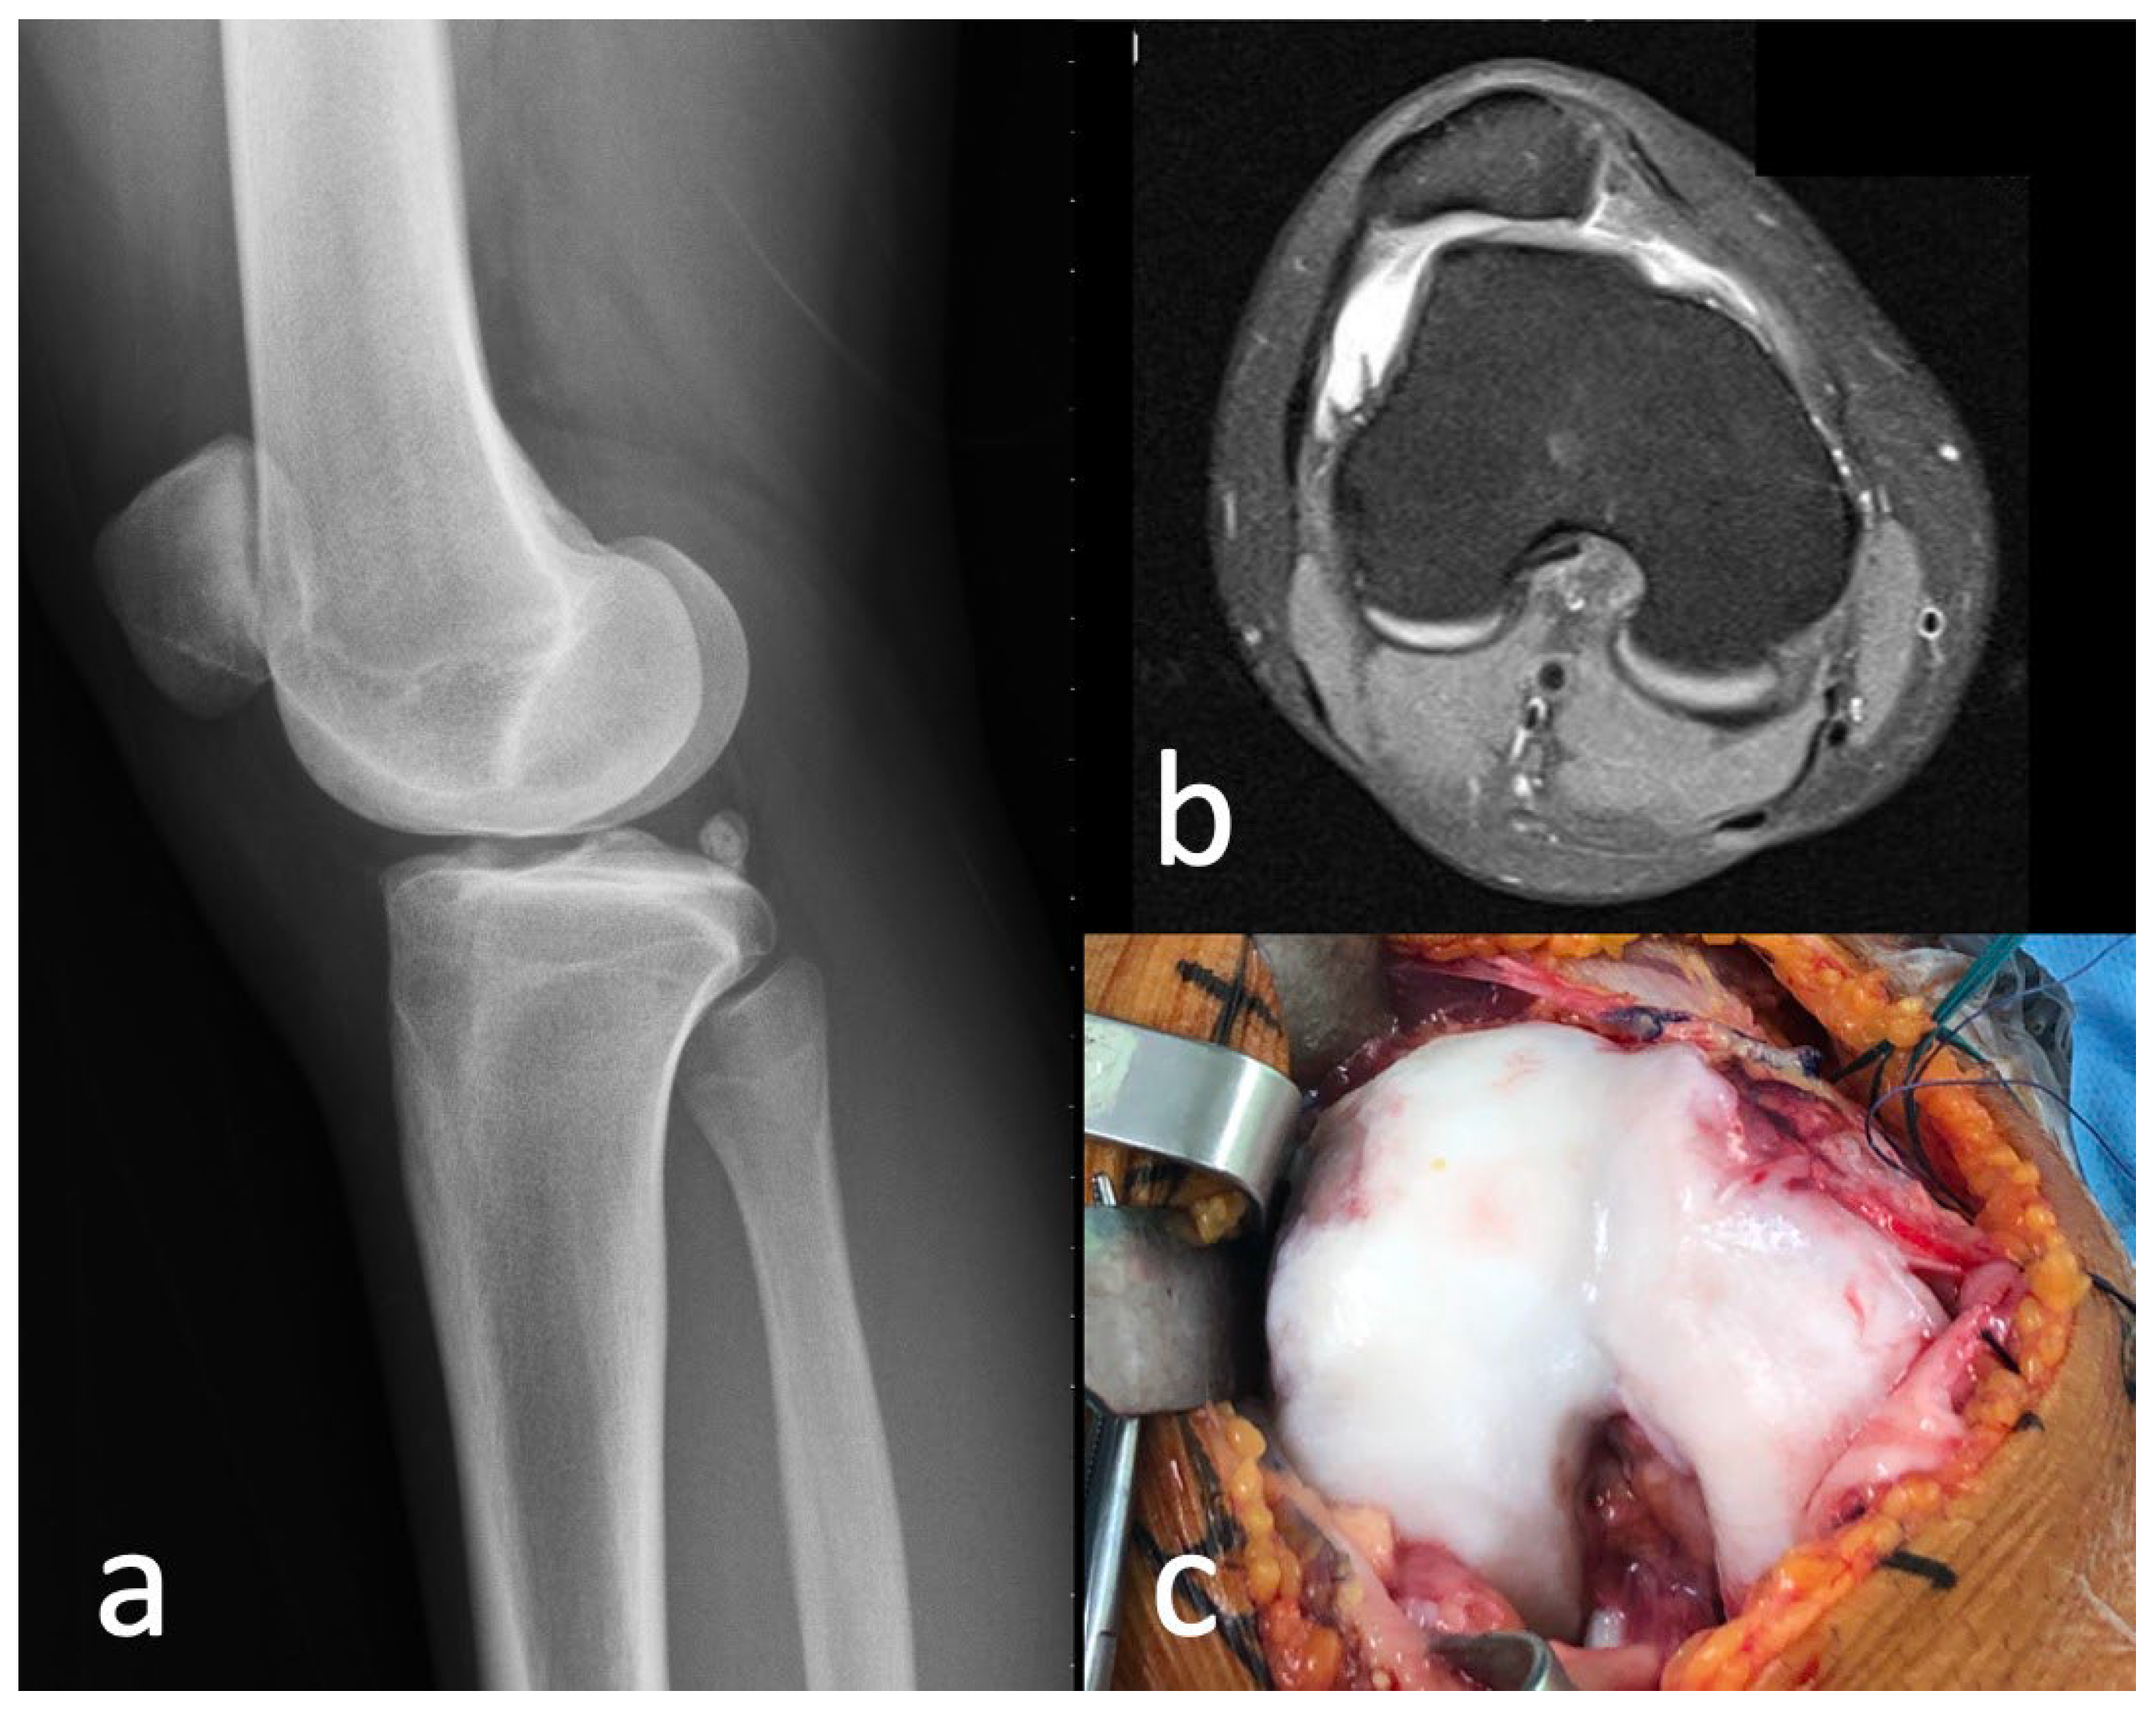

2.1. Case